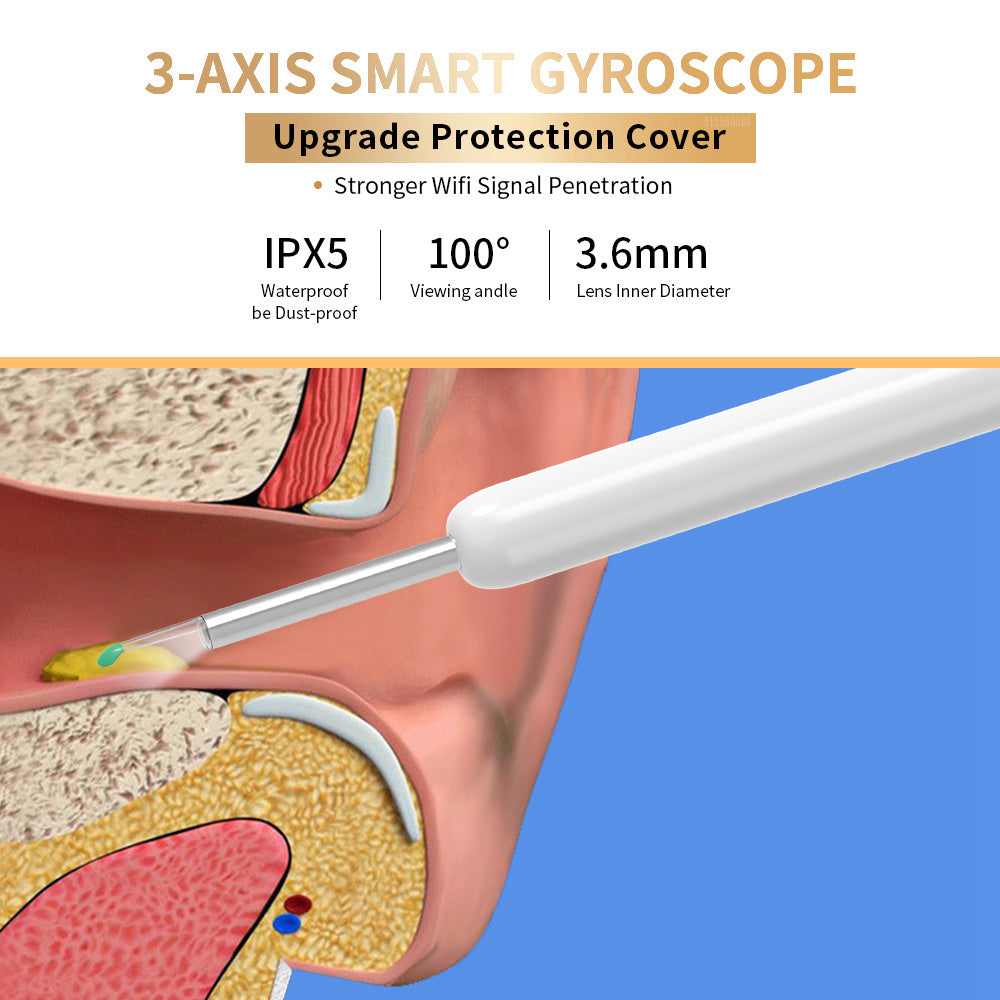

🔹 Wide-Angle Lens – Enhanced field of view for full ear inspection.

🔹 Water-Resistant & Durable – Easy to clean with IPX5 splash-proof protection.